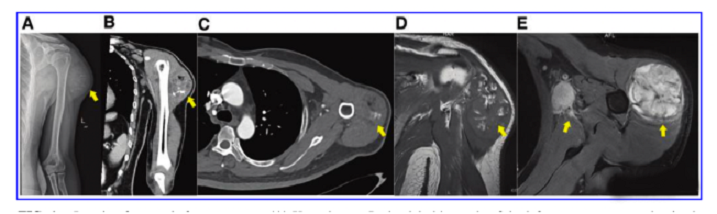

接受iPS細(xì)胞治療患者的畸胎瘤。(A) 在左上臂的三角肌中,觀察到一個(gè)圓形的混合密度腫塊,邊界不清,為9.6±5.2cm。(B) CT冠狀掃描顯示三角肌內(nèi)有一圓形混合密度腫塊,邊界不清。(C)增強(qiáng)CT軸向掃描顯示不均勻和中度強(qiáng)化。(D)MRI T1W以等信號(hào)為主,有不規(guī)則的高低信號(hào)區(qū)。(E) T2W也顯示高信號(hào)和斑片狀低信號(hào)區(qū),左腋窩有多個(gè)淋巴結(jié)腫大。